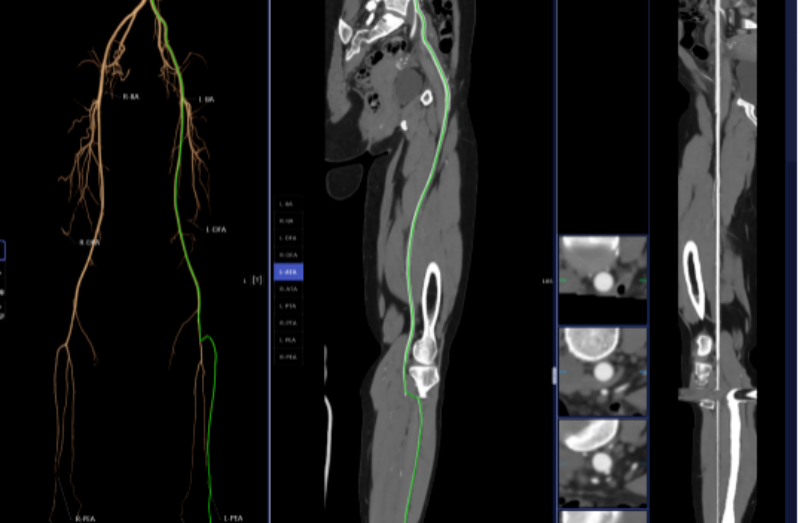

血管診斷、腦血管灌注成像

頭頸部CTA、冠狀動脈CTA、肺動脈CTA及肢體CTA是一種無創(chuàng)、低風險、快速的檢查方法,能夠清晰識別血管狹窄、畸形或斑塊,明確病灶與周圍正常組織的位置關系,為治療方案的制定提供有力依據(jù),能提高患者生存率,縮短高危患者急救救治時間。

以往,放射科醫(yī)生進行頭頸部CTA和冠狀動脈CTA重建后處理,需要醫(yī)生應用工作站手動處理,耗時約20-30分鐘。而AI人工智能輔助診斷系統(tǒng)通過計算機視覺和深度學習技術,僅需5-10分鐘即可完成影像重建的后處理計算,一鍵生成精準的三維重建圖;系統(tǒng)還能自動標記血管名稱、快速判斷斑塊性質(zhì),并根據(jù)最新指南對狹窄程度進行分級診斷等,幫助醫(yī)生快速定位病變節(jié)段,準確分析斑塊類型及狹窄程度;對腦血管灌注成像進行快速重建和診斷,大幅縮短患者等候檢查和獲取診斷報告的時間。